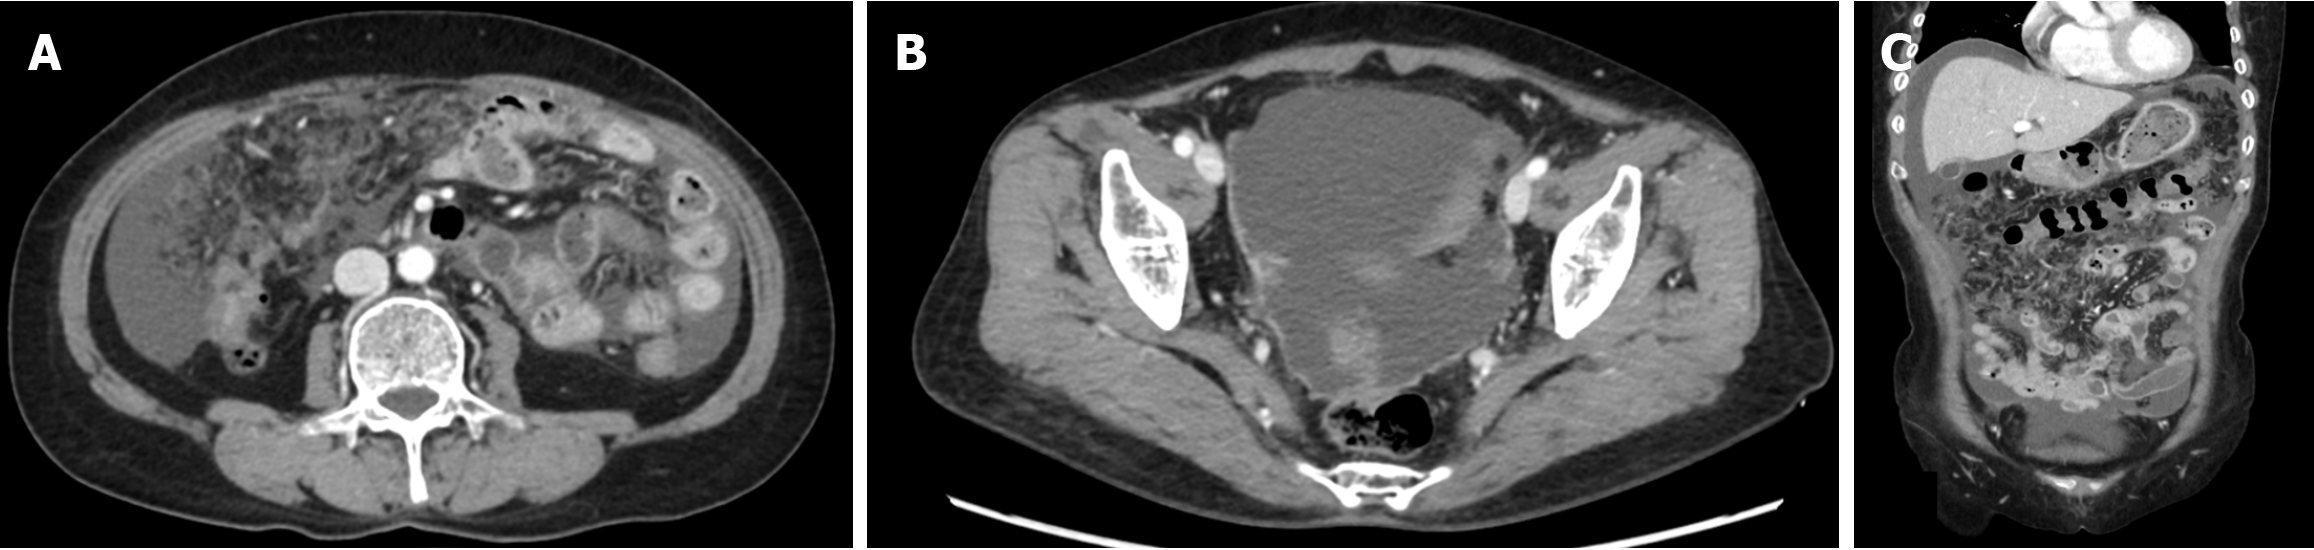

Abdominal-pelvic (AP) computed tomography (CT) revealed moderate to large volumes of diffuse ascites; smudged, nodular omentum in the abdomen and pelvic cavity; and focal abutting or invasion of the anterior wall of the mid-rectum in the cul-de-sac area (Figure 1). An ulcerofungating mass (4 cm in diameter) was observed 45 cm from the anal verge during colonoscopy (Figure 2A), and the histological results confirmed moderately differentiated adenocarcinoma. Positron emission tomography (PET)-CT revealed a substantially elevated metabolic uptake in the abdomen, suggestive of peritoneal seeding (Figure 3).

For patients with CRC and PM, CT is the predominant imaging modality for the evaluation of tumor size and extent, with a reported sensitivity of 75%, specificity of 92%, positive predictive value of 90%, and negative predictive value of 79% for 64-row CT[25]. The reported average sensitivity is 89% for lesions ≥ 0.5 cm, whereas it was merely 43% for those measuring < 0.5 cm[26]. Additionally, CT-based assessment of factors determining complete resection of the neoplasm remains challenging, as the detection rate for tiny, localized lesions, such as diffuse peritoneal, small-intestinal, and mesenteric involvement, is low. To compensate for the low detection rate of CT in these regions, magnetic resonance imaging and PET-CT examinations are conducted, but they remain sufficient. In this case, although the smudged, nodular omentum upon CT and the significantly elevated metabolic uptake in the relevant area upon PET-CT were suggestive of peritoneal carcinomatosis, the diffuse peritoneal, small-intestinal, and mesenteric involvement could not be anticipated preoperatively.